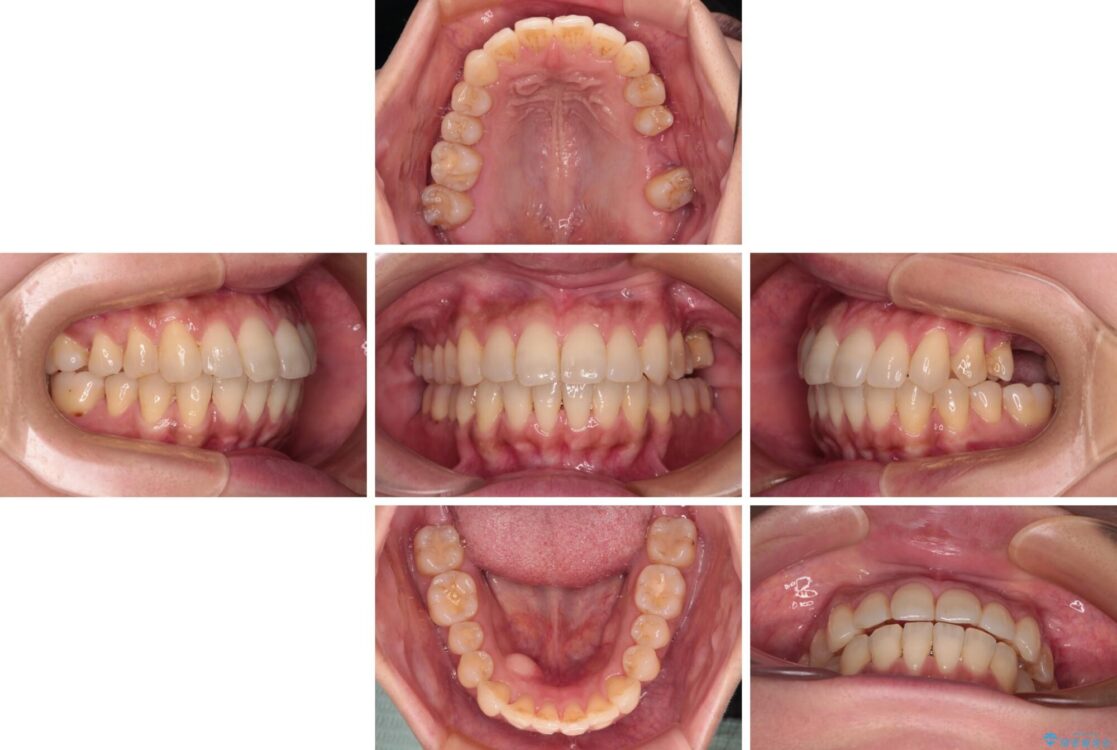

治療後

• インビザラインによる矯正治療と奥歯のインプラント治療 治療後画像

治療後について

歯の傾斜が改善され、インプラントによるクラウンが装着されたことで、物が挟まることもなくなりました。